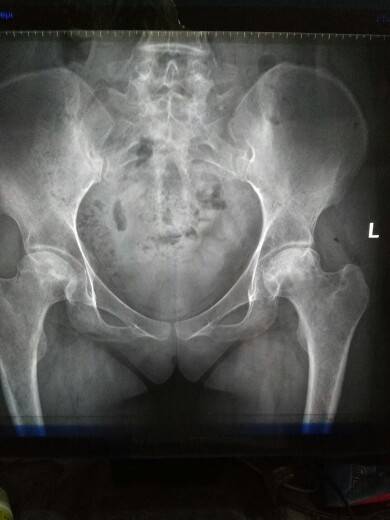

复查结果

今天从早上六点多钟起床忙的给孩子做饭,送孩子上学,七点多钟出发八点多钟到医院十一点整所有的结果都出来了,还算顺利。结果也算理想,就是骨坏的腿实在不想动,累到本宝宝了。

那个片子显示骨坏了吗?

医生怎么说 骨坏好些了吗